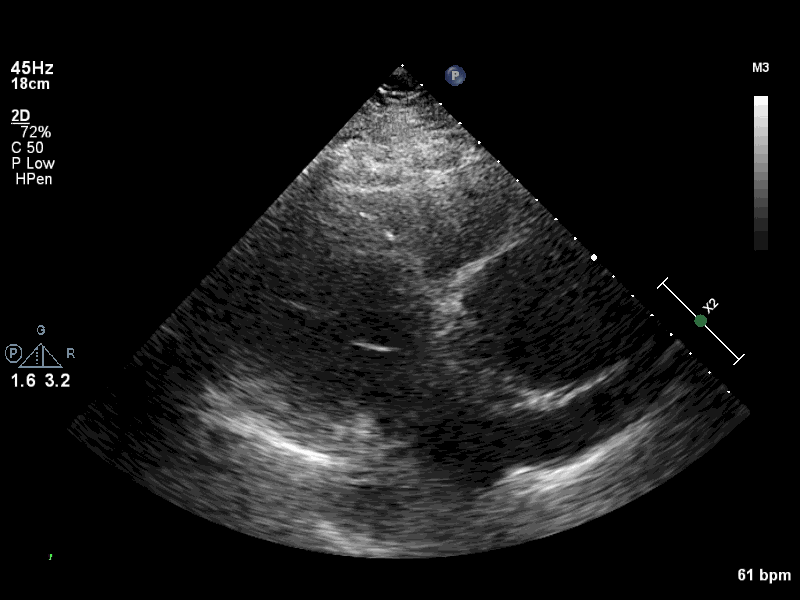

Visual Examples

PLAX Example 1 PLAX Example 2 PLAX Example 3 PLAX Example 4